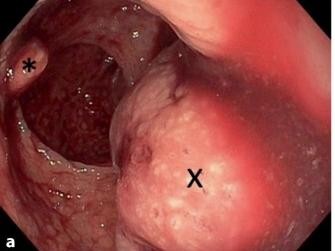

Kindernotfall: 7-Jähriger mit akuter rektaler Blutung

Bei einem 7-jährigen Jungen war ohne traumatisches Ereignis eine akute rektale Blutung aufgetreten. Sprachentwicklungsverzögerung, Makrozephalie und muskuläre Hypotonie sind bekannt, aber nicht die Ursache. Ein seltenes genetisches Syndrom erklärt die aktuellen und früheren Befunde.

Infantile systemische Hyalinose/© C. Hempel und O. Hempel/ all rights reserved Springer Medizin Verlag GmbH, Auf einem Computer werden genetische Daten angezeigt/© nicolas_ / Getty Images / iStock (Symbolbild mit Fotomodellen), Abgerissener Rektumpolyp und blutender Stumpf/© Kolb K, Seul R / all rights reserved Springer Medizin Verlag GmbH, DNA-Molekül-Modell/© AF-studio / Getty Images / iStock (Symbolbild), Kongenitale Zehenfehlstellung („Hallux valgus“)/© Semler O, Hoyer-Kuhn H / all rights reserved Springer Medizin Verlag GmbH, Abbildung Vertex Casgevy/© Vertex Pharmaceuticals (Germany) GmbH, Pipettieren von Proben unter Sterilbank/© salomonus_ / stock.adobe.com (Symbolbild mit Fotomodell), Person zeigt mit Stift auf PCR Befund/© Pgiam / Getty Images / iStock (Symbolbild mit Fotomodell), Bei einem Jungen wird ein EKG durchgeführt/© ulianna19970 / stock.adobe.com (Symbolbild mit Fotomodell), Trockenblutkarte für Neugeborenenscreening/© Stefan Sauer / dpa, Rötlich-violette Papeln/© Dr.med.J.P.Müller / OKAPIA KG / / picture alliance (Symbolbild mit Fotomodell), Vierjähriges Kind auf Arm der Mutter/© laura clay ballard / Getty Images / iStock (Symbolbild mit Fotomodell), 17-jährige Patientin mit familiärer intrahepatischen Cholestase/© Eickhölter H et al. / all rights reserved Springer Medizin Verlag GmbH, Search Icon, Die Leitlinien für Ärztinnen und Ärzte, Endoskopische Befunde des Magenkarzinoms/© Probst, A., Messmann, H. / all rights reserved Springer Medizin Verlag GmbH, Hand hält Laborröhrchen/© Kunstzeug / stock.adobe.com (Symbolbild mit Fotomodell), Radiologin richtet Mammographiescreening ein/© LIGHTFIELD STUDIOS / stock.adobe.com (Symbolbild mit Fotomodellen)